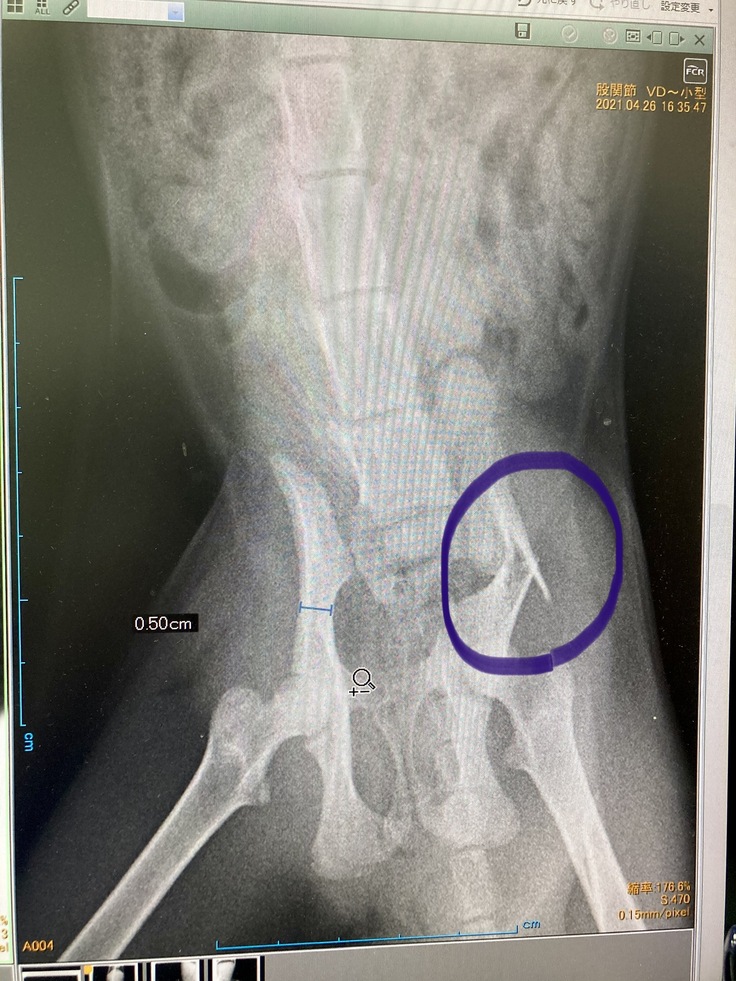

骨盤と左大腿骨の2箇所を骨折しており、すぐにでも手術が必要な状態でした。

骨盤骨折(左写真)で当初肛門が圧迫され狭まっており、便排出が

出来ない恐れもあり、それを広げる手術が必要になる可能性もありました。

4/28 金属プレートで骨を固定する手術をしました。幸いにも排便に支障がある程の状況迄至らず無事に手術は成功しそのまま安静の為入院となりました。

・治療・手術内容:骨盤、左大腿骨骨折によるボルト固定手術・入院・抜糸・完治後ボルト摘出

骨盤と左足骨折の手術